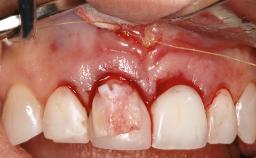

Treatment of Peri-Implantitis at a Zirconia Implant

Frank Schwarz, Ausra Ramanauskaite

Due to their promising clinical performance, zirconia implants have recently become popular alternatives to titanium implants, particularly for areas with high esthetic demands (Holländer and coworkers 2016; Roehling and coworkers 2016; Lorenz and coworkers 2019). However, regardless of the reported high survival and success rates, zirconia implants were affected by peri-implant diseases over the short observation period, suggesting the importance of treating peri-implant diseases at zirconia implants (Becker and coworkers 2017). In their case, Frank Schwarz and Ausra Ramanauskaite present 3-year results following mechanical debridement alongside Er:YAG laser monotherapy.